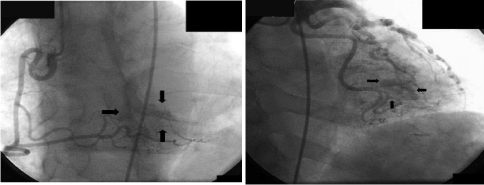

We describe case of a 67-year-old male patient with a history of tobacco and cocaine abuse who presented to the Emergency Department with shortness of breath occurring both at rest and with exertion. Vital signs showed HR of 110bpm, BP 118/70mmHg, respiratory rate of 20/min, O2 saturation of 96% on 2L of oxygen. Physical examination was remarkable for S3 gallop with mild rales over b/l lung. EKG showed sinus tachycardia with significant ST Elevation in leads V2-V5 with significant Q waves in V2-V4. Serial cardiac biomarkers were minimally elevated at 0.9ng/ml. Coronary angiography showed normal epicardial coronary arteries; however, during selective angiography of all 3 major coronary arteries, there was extensive draining of the contrast agent into the Left Ventricular (LV) cavity through many small, diffuse fistulae, resulting in complete LV contrast opacification (Figure 1). Hence, we diagnosed coronary cameral fistula involving all the 3 coronary arteries with each of them draining into LV. The shunt didn’t appear to be large and patient also didn’t complain of any exertional angina, so there was no coronary steal phenomenon and no acute intervention was deemed necessary at this time. Transthoracic echocardiogram revealed decreased LV ejection fraction of 35-40% with a thin akinetic septal and anteroseptal wall (Figure 2). His presentation was consistent with acute systolic heart failure due to prior MI and ischemic cardiomyopathy. He was discharged after improvement with a follow up in 1 week for electrophysiologic studies and possible intra cardiac defibrillator placement.

Figure 1: Panel A - Coronary angiography shows no lesions in epicardial coronary arteries; but there are multiple CCF arising from diagonal artery and obtuse marginal artery draining into the LV cavity (black arrows). Panel B - Coronary angiography shows no lesion in right coronary artery but there are multiple CCF arising from right posterior descending artery again draining into the LV cavity (black arrow).